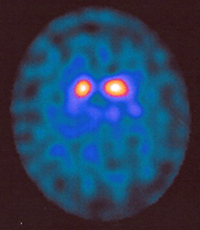

Was ist ein DaTSCAN?

Ein DaTSCAN ist eine Hirnszintigraphie, genauer: eine Dopamin-Rezeptor-Szintigraphie. Diese Untersuchung wird durchgeführt zum Nachweis oder Ausschluß eines Morbus Parkinson. Bei Parkinson-Syndromen und einigen Demenz-Erkrankungen gehen Nervenzellen in der sog. Substantia nigra im Mittelhirn zugrunde (Degeneration dopaminerger Nervenzellen). Die bildliche Darstellung der Substantia nigra ermöglicht eine exakte Diagnosestellung und damit gezielte medikamentöse Therapie.

Deutlich verminderte Aktivitätsspeicherung im Bereich der Stammganglien. Fortgeschrittenes Parkinson-Syndrom.

Zur Vorbereitung auf die Untersuchung erhalten Sie bei uns zunächst Irenat-Tropfen, um eine Radioaktivitätsaufnahme in die Schilddrüse zu blockieren. Einige Zeit danach wird eine mit Jod-123 markierte Substanz in eine Armvene injiziert, die sich im Bereich des Mittelhirns/der Substantia nigra anreichert. Nach drei Stunden werden Aufnahmen des Schädels angefertigt, wobei die Gammakamera um den Kopf kreist. Die Untersuchung dauert etwa 45 Minuten.